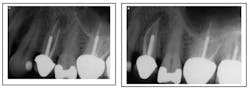

Missed third canal in upper first premolar